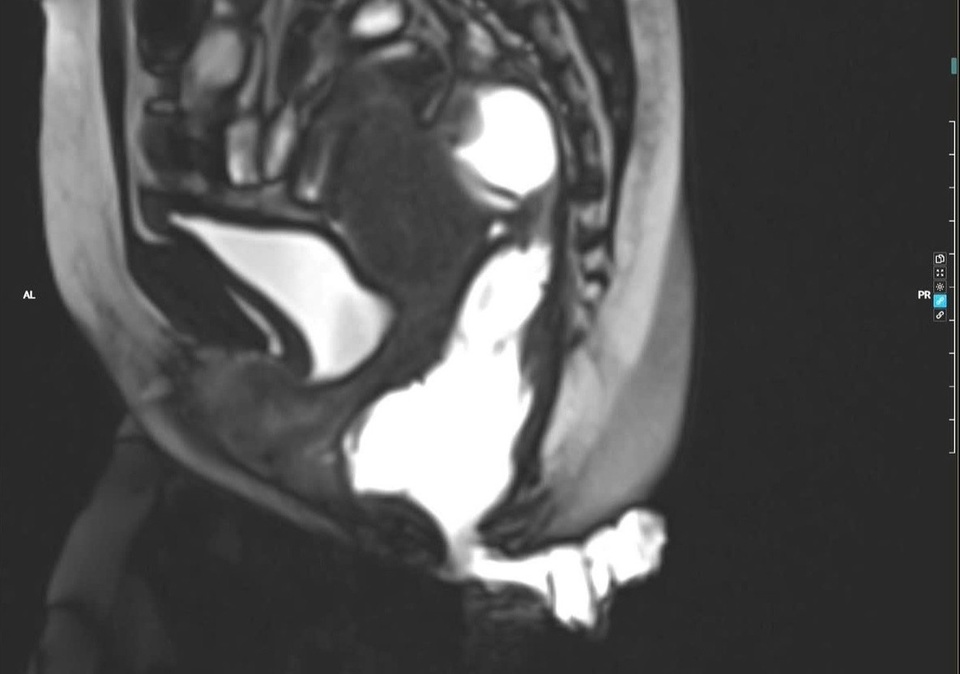

Hình ảnh chụp cộng hường từ động tống phân cho thấy hình ảnh túi sa thành trước trực tràng kiểu túi, sa nhẹ bàng quang. Ảnh: BVCC.

Khi đến khám tại Bệnh viện Trung ương Quân đội 108, bệnh nhân được chỉ định thực hiện các thăm dò chuyên sâu, trong đó có chụp cộng hưởng từ động tống phân (Defecography MRI) để đánh giá toàn diện chức năng sàn chậu. Kết quả cho thấy người bệnh mắc nhiều bệnh lý phối hợp: táo bón do sa thành trước trực tràng kiểu túi độ III, trĩ hỗn hợp độ IV, nứt kẽ hậu môn mạn tính sau tiêm xơ trĩ và són tiểu mức độ nhẹ.